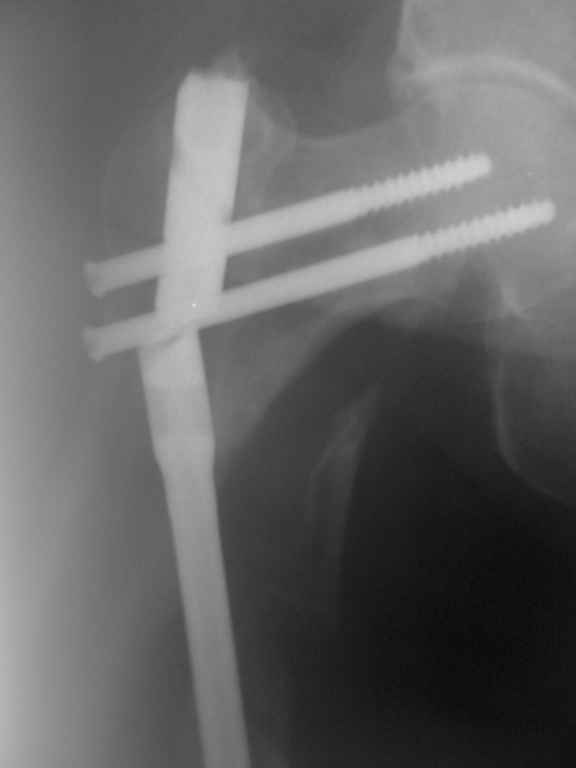

Пациентка 69 лет. травма в ДТП год назад. Оскольчатый перелом бедра.

выполнен остеосинтез штифтом. 2 недели назад вставая с постели почувствовала резкую боль в области перелома.

Р-гр в приложении.